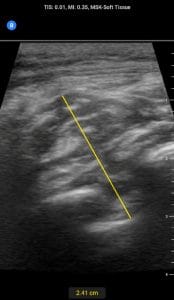

Lastly, with this November 2022 issue there emerged a theme in the case files and case reports: soft tissue examination using POCUS. Sheeka, et al. describe a diagnostic radiology case of a retained foreign body, but this is very important for POCUS users to learn from. Kaiyasah,et al. describe POCUS application in pilonidal sinus disease, a novel application for this common disease entity. Freilich et al. present a case of a soft tissue mass that was highly vascularized on POCUS examination, surprisingly found to be a post-traumatic AVM. McCreary, et al. describe the POCUS findings in a young patient with extraosseous Ewing’s sarcoma in the neck. Taken together, these cases highlight how usefully POCUS is in soft tissue examination beyond basic indications such as evaluating cellulitis for underlying abscess. While some of the above entities might be “rare”, POCUS users who scan soft tissue should be aware of these cases and use the discussion to expand their differential diagnosis of soft tissue findings accordingly.